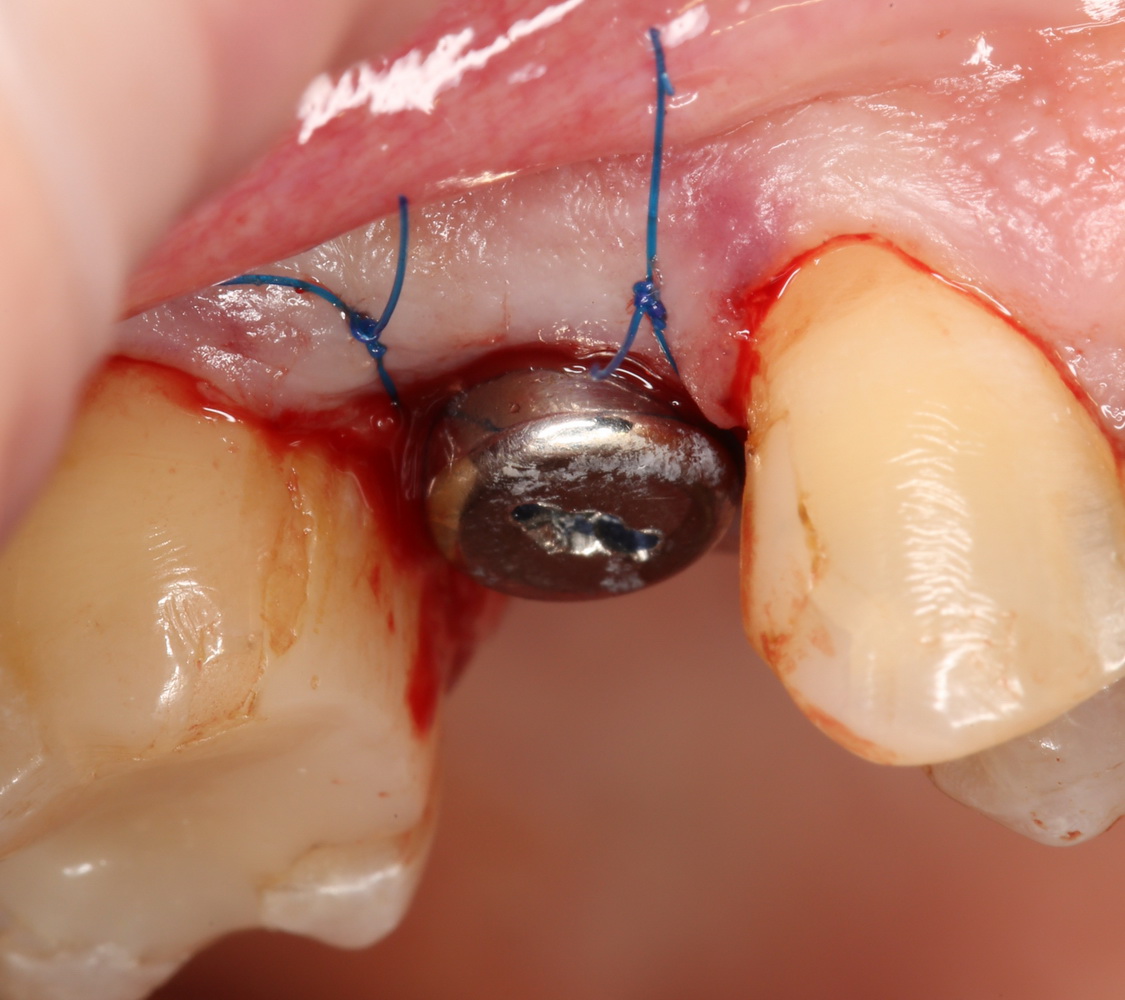

После перкуторной проверки стабильности имплантатов и точности позиционирования, мы переходим к следующему этапу — сохранению десневого контура.

Установка имплантатов занимает около двух минут.

Сохранение десневого контура

Для этого мы используем индивидуализируемые временные абатменты Esthetic Cap треугольного сечения, являющиеся уникальной разработкой Xive. Об их преимуществах для решения подобных задач можно прочитать здесь>>, а тема формирования и сохранения десневого контура подробно раскрыта тут>>. Очень рекомендую прочитать.

Абатменты позиционируются в трех положениях, потому мы заранее выровняли платформу по граням. Усилие, с которым устанавливаются абатменты, не превышает 10-14 Нсм.